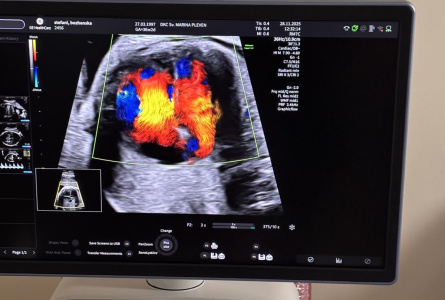

Клиника по акушерство и гинекология

Клиника по образна диагностика